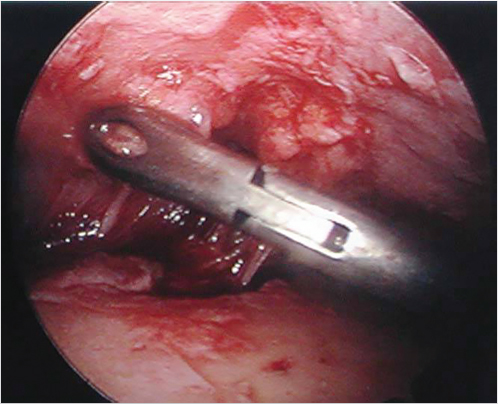

The marked skin and subcutaneous tissue are excised above the musculo-aponeurotic tissue. The galea and the periosteum are bluntly separated with a closed hemostat dissecting along the muscle fibers to avoid damage of the local sensory nerves. Using a curved periosteal elevator, the subperiosteal dissection extends to the supraorbital rims and to the frontotemporal line (Fig. 21‑3). Dissection is extended to the nasal tip to release the procerus. Direct visualization is obtained using a lighted rigid endoscope (Fig. 21‑4) and endoscopic video monitor (Fig. 21‑5). An optical cavity is created using a sheath around the scope to elevate the soft tissue off the lens. In addition, three nylon suspension sutures are placed externally just above the brow line (Fig. 21‑6). Divergent traction is placed on the sutures. The traction on the sutures helps create an optical cavity.

The supraorbital periosteum is divided completely to the level of the lateral orbital rims with an endoscopic carpal tunnel hook knife scalpel. Resection of the corrugators, procerus, and other depressors is achieved bluntly with a grasping forceps. The supratrochlear and supraorbital nerves are identified and preserved. The glabellar region is inspected after resection to ensure that the contour is smooth and not depressed or irregular. If there is any depression, a small amount of fat or SMAS can be used to fill the area (Fig. 21‑7, Fig. 21‑8, Fig. 21‑9).